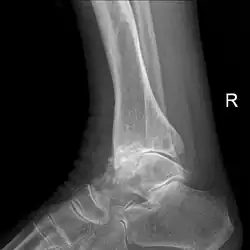

Diagnosis is made with reasonable certainty based on history and clinical examination.[52][53] X-rays may confirm the diagnosis. The typical changes seen on X-ray include: joint space narrowing, subchondral sclerosis (increased bone formation around the joint), subchondral cyst formation, and osteophytes.[54] Plain films may not correlate with the findings on physical examination or with the degree of pain.[55]

Severe osteoarthritis and osteopenia of the carpal joint and 1st carpometacarpal joint -

Primary osteoarthritis of the left knee. Note the osteophytes, narrowing of the joint space (arrow), and increased subchondral bone density (arrow). -